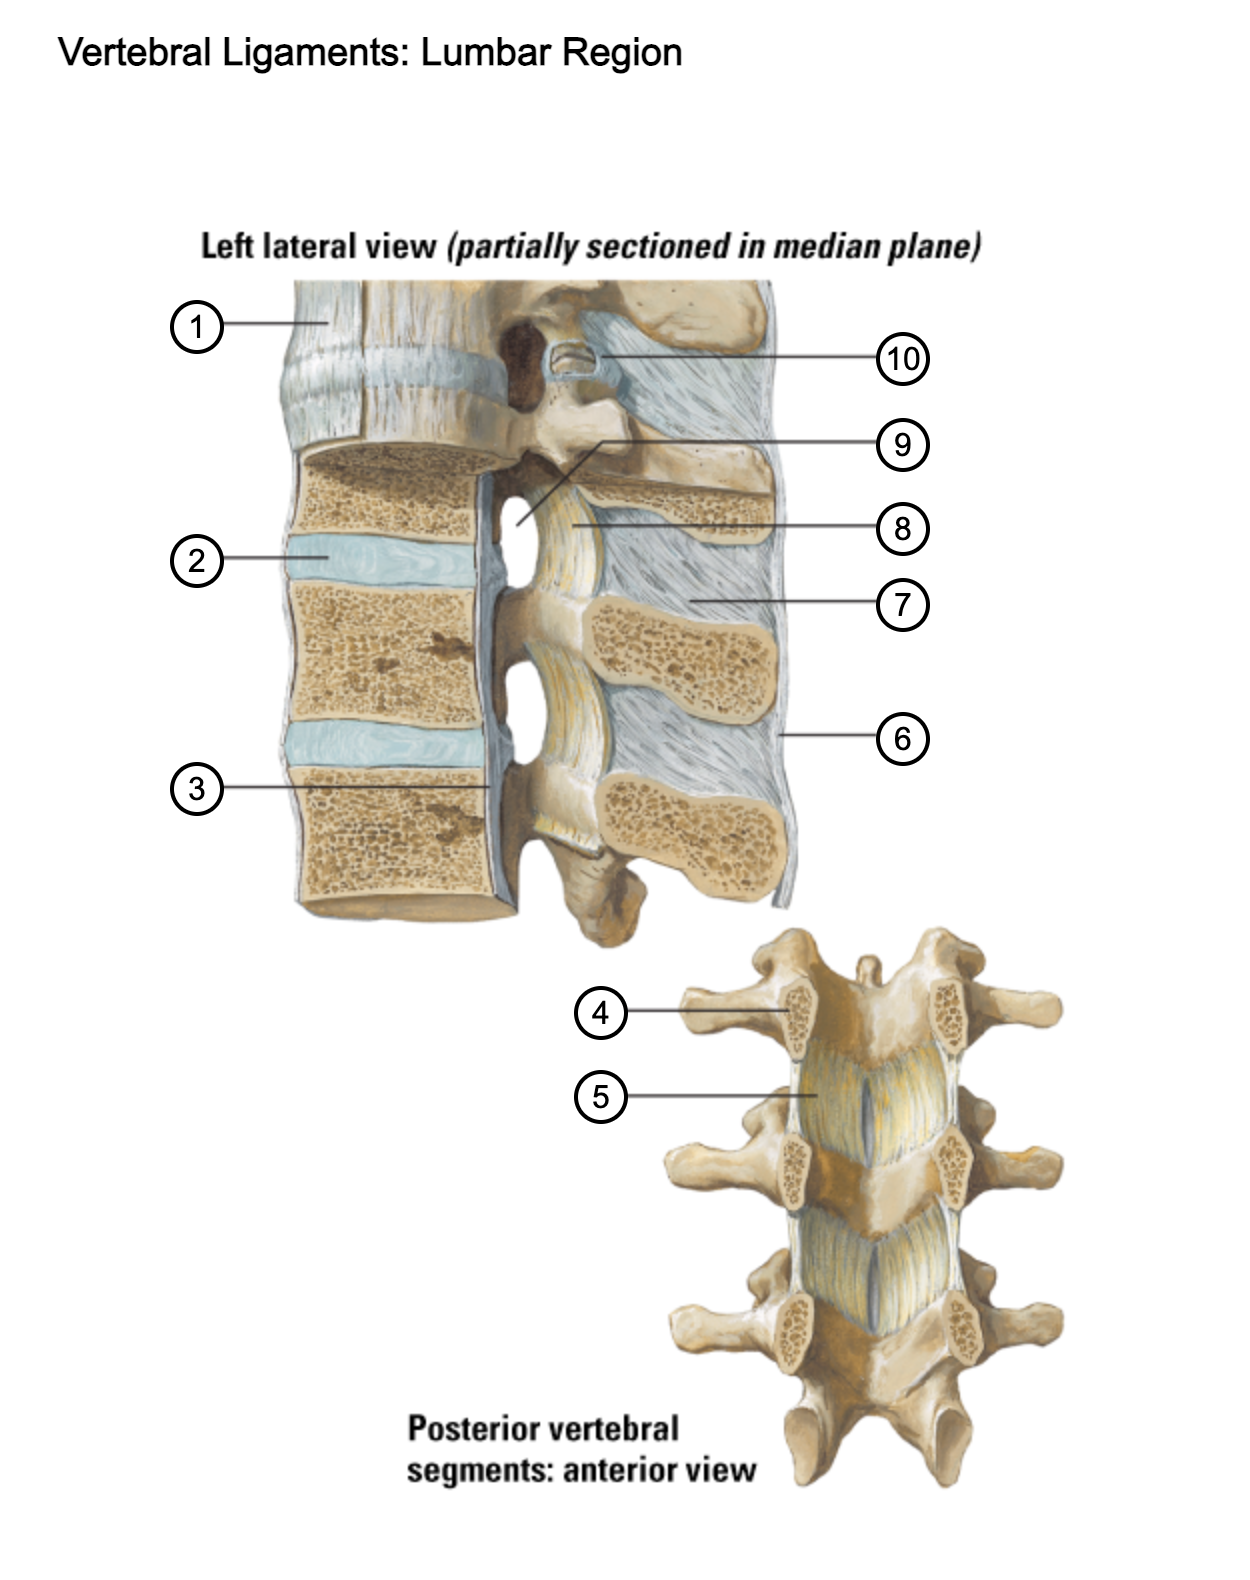

1

anterior longitudinal ligament

2

intervertebral disc

3

posterior longitudinal ligament

4

pedicle (cut surface)

5

ligamentum flavum

6

supraspinous ligament

7

interspinous ligament

8

ligamentum flavum

9

intervertebral foramen

10

capsule of zygapophysial join (partially opened)